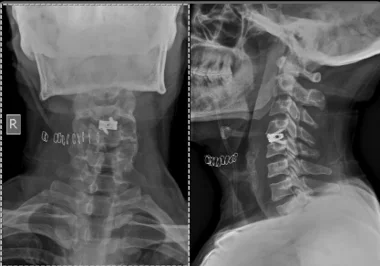

Before & After Clinical Gallery

We showcase real patient cases (with consent), including:

• Pre- and Post-operative MRIs and X-rays

• Disc Herniations, Stenosis, and Spondylolisthesis cases

• Visible improvement in alignment and decompression

Before

After